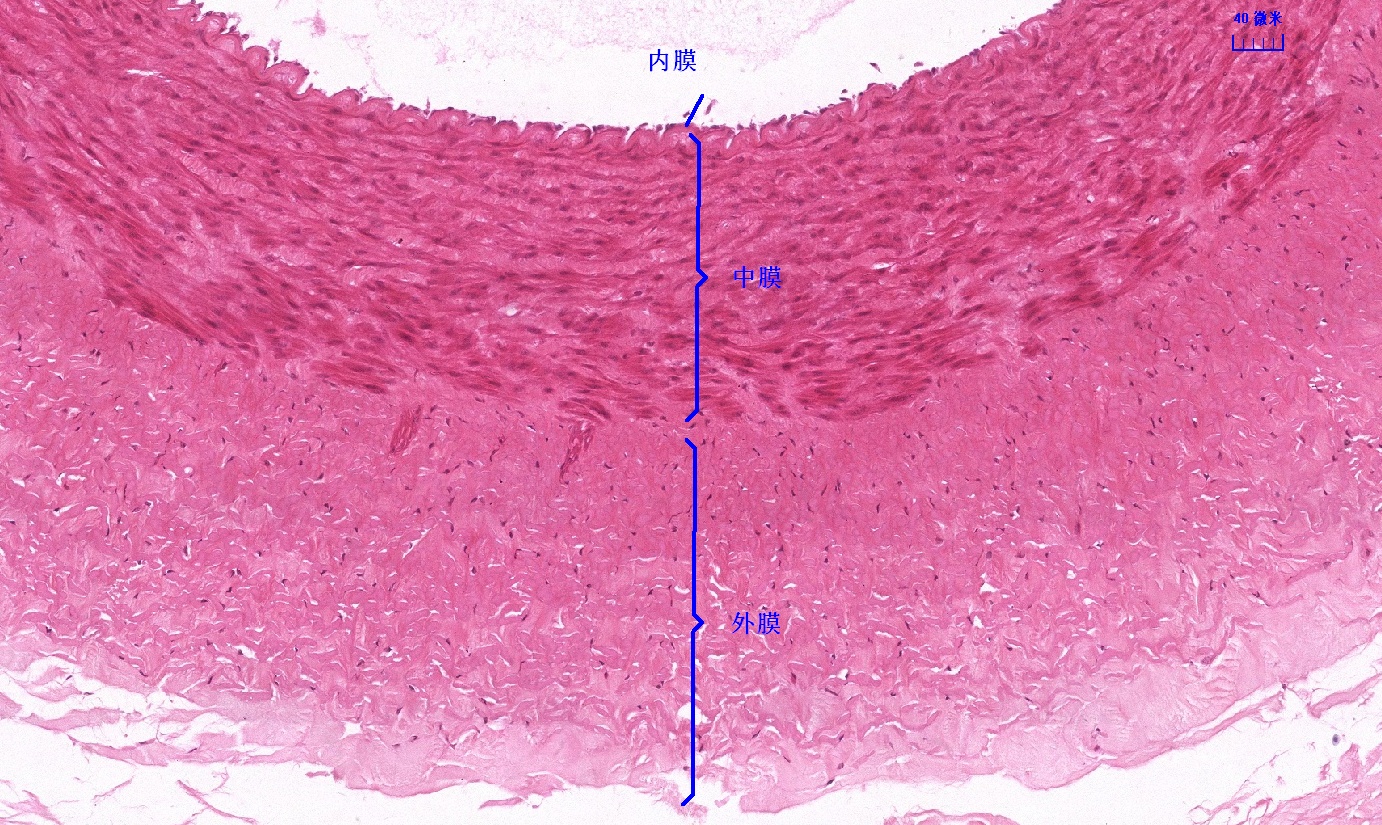

6.1 循环系统切片库